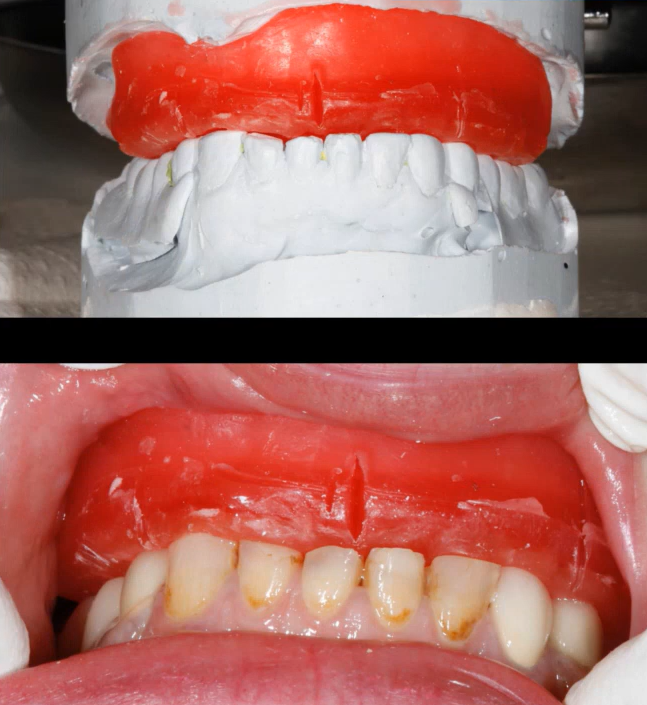

- Analysis of interocclusal distances. In cases of complete edentulism, the bite block method remains the most accurate method today. However, anthropometric measurements help make the model more accurate and avoid excessive or insufficient height of future prostheses.

Basic techniques for recording interocclusal height for creating future prostheses, top to bottom: anthropometric measurements, working with a Full-Arch bite block. YouTube/ Dr. Sergey Rozhnov /sergiodontologist

If there are remnants of teeth or old prostheses, the task is easier, but the volume and complexity of the work remain high. In the images below are several examples of restorations.

A PFM mandible prosthesis supported by 4 implants – optimal height of the Full-Arch prosthesis. YouTube/ Dr. Sergey Rozhnov /sergiodontologist

The images above show a classic PFM prosthesis supported by four implants. The restoration has been successfully in place for over five years. This is an example of optimally executed work, considering the height and overall configuration of the prosthesis. Such a prosthesis will not act as a massive lever and transfer excessive load to the implants. However, it is not ideal either. Given the volume of the metal frame, veneering material will be thin. This results in frequent chips, cracks, and frequent requests for correction.The following images show a much more complex situation. This is a temporary denture for immediate loading, made directly without the need for a dental laboratory. Note the height of this denture.